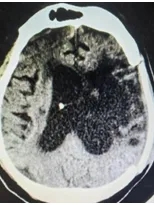

▲ 左图入院CT;右图颅骨修补及脑室分流术后复查CT

稳定病情后,(高压氧、中医中药、促醒西药、气管镜吸痰、无创神经调控等治疗)共2月余,患者肺炎逐渐稳定、交感神经过度亢进发作次数减少、颅压下降,生命体征稳定;但患者昏迷评分仍很低、重度异常脑电图。

经传统促醒手术:颅骨修补手术、脑积水分流手术,再次复查脑功能磁共振、昏迷脑电图评估后,昏迷评分较前提高。经科室讨论,神经外科一病区寿记新主任总结指出:该患者可先行短时程脊髓电刺激手术治疗,若治疗效果明确,可行二期电极及刺激器永久植入。2024年11月13日,小王完成了短时程脊髓神经刺激测试电极置入手术。